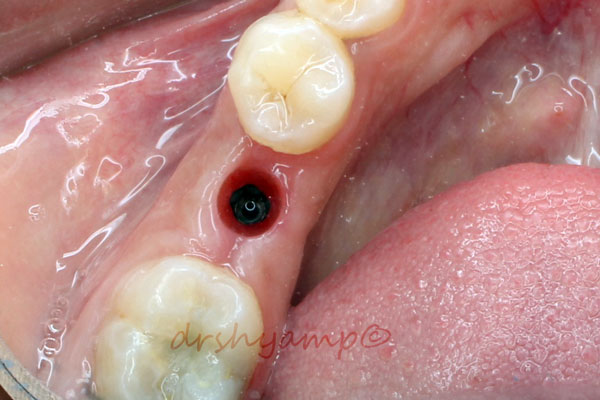

immediate dental implant

-

immediate dental implant